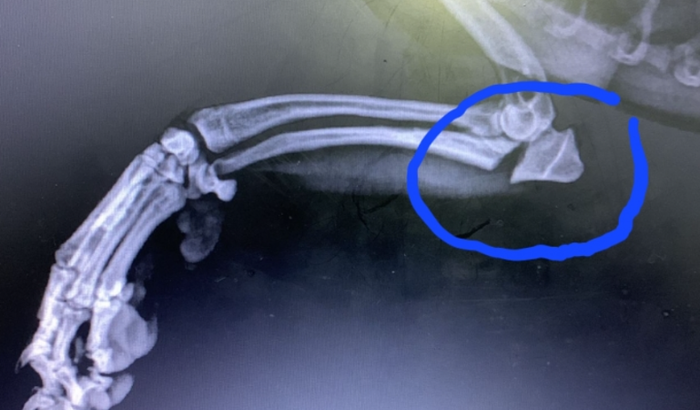

Flash caiu da sacada e quebrou a patinha da frente. A cirurgia precisa ser feita com urgência, estamos fazendo a vakinha para que possamos fazer o quanto antes. Qualquer ajuda será bem vinda. ver tudo

Flash caiu da sacada e quebrou a patinha da frente. A cirurgia precisa ser feita com urgência, estamos fazendo a vakinha para que possamos fazer o quanto antes. Qualquer ajuda será bem vinda.